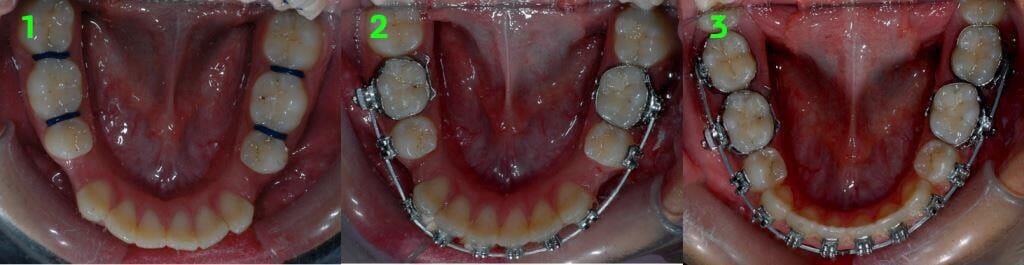

טיפול אורתודונטי שגרתי

כאמור, רוב טיפולי יישור השיניים מתחילים בגילאי 12 – 13 כאשר השיניים סיימו את התחלפותן או נמצאות לקראת סיום ההחלפה שלהן. טיפול כזה מבוצע לרוב באמצעות מכשור קבוע ("קוביות", "גשר") המודבק לשיניים למשך זמן הטיפול. טיפול כזה כולל בד"כ מספר שלבים שיכולים להתבצע בו- זמנית או בסדר שונה מהמתואר להלן:

• הרחבת הקשת העליונה, במידה וישנו צורך כזה. לרוב תבוצע באמצעות מכשירים אשר מותקנים באזור החך.

• הדבקת סמכים (לרוב מתכתיים) על השיניים. לאחר הדבקת הסמכים מבוצעות הפעלות של המכשיר הקבוע ("מתיחות"), במטרה לבצע את הפעולות הבאות:

1. סידור קשתות השיניים- במידה והבעיה העיקרית של המתרפא היא שיניים עקומות, הרי שעיקר השיפור יושג כבר בשלב הזה.

סידור קשתות השיניים

2. הזזת שיניים לאורך הקשתות - למשל על מנת לסגור מרווחים בין השיניים.

הזזת שיניים בטיפול אורתודונטי

הזזת שיניים